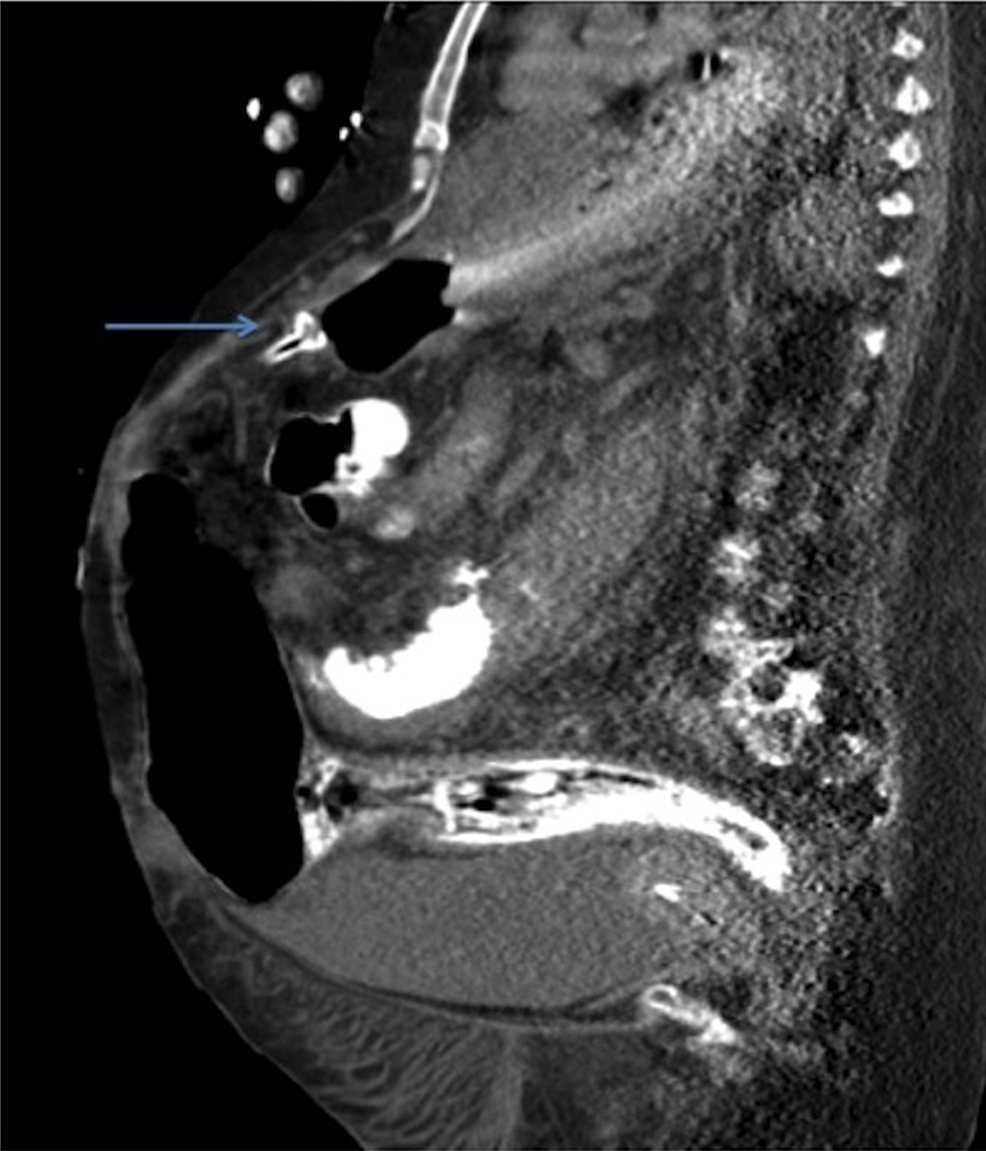

From www.cureus.com

Cureus The Buried Bumper Syndrome A Catastrophic Complication of Peg Tube Erosion Patient traction on tubing and weight gain predispose to the internal peg bumper eroding through the anterior gastric wall and becoming buried, leading to the condition generally known. Percutaneous endoscopic gastrostomy (peg) is a safe and widely used method of providing enteral nutrition in patients. If a gastrostomy tube is dislodged, replacement should be attempted within 24 to 48 hours. Peg Tube Erosion.